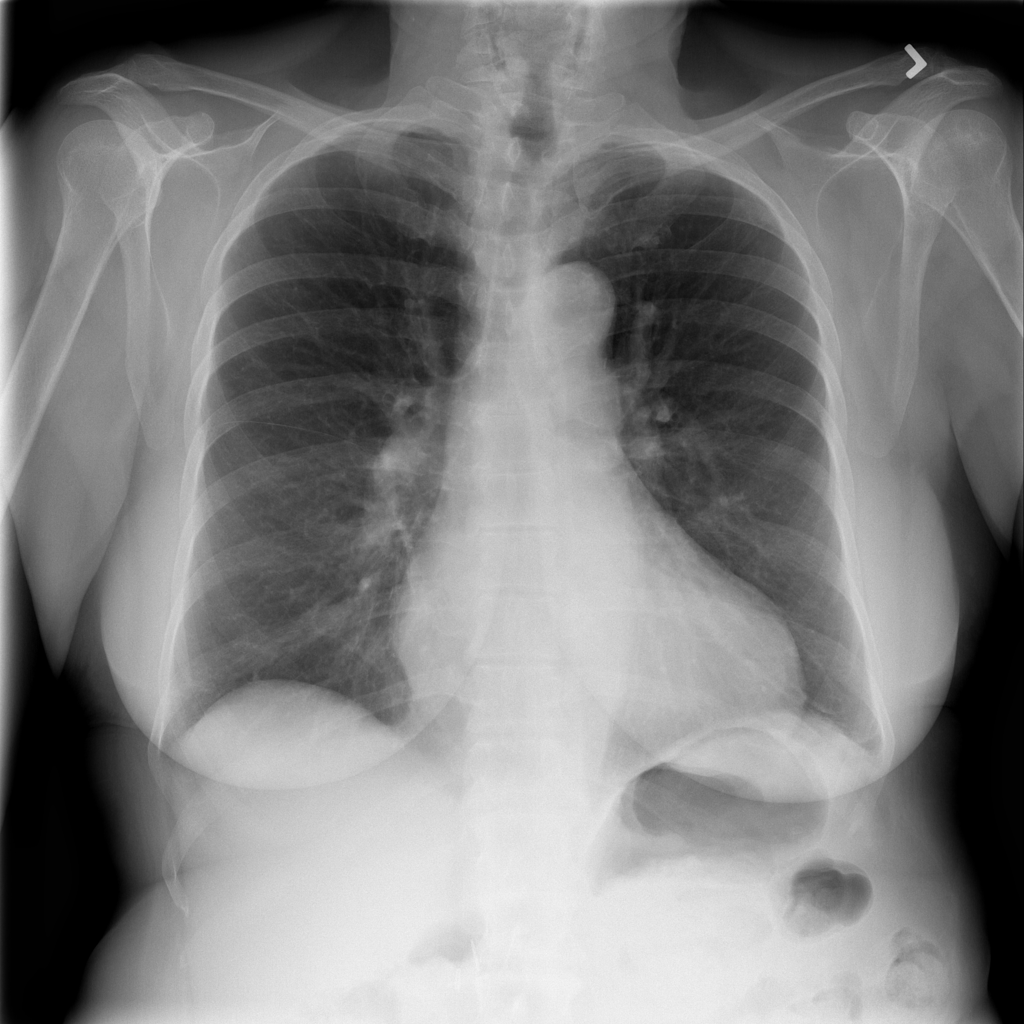

PAT-4639 · IMG-045Cardiomegaly

PAT-4639 · IMG-045

PA